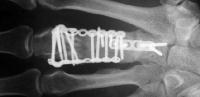

I removed this hardware, and used two mini condylar blade plates at right angles to resecure the distal bone juncture. This allowed more distal purchase while avoiding hardware placement beneath the metacarpal head extensor hood. I replated the proximal bone juncture although it looked clinically healed - not worth taking a chance.

Final result, eight months postop, healed:

Healed.